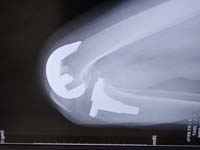

片側人工膝関節 / UKA

関節の半分の人工関節が片側人工関節(UKA;Unicompartmental Knee Arthroplasty)です。

1990年代まではUKAの長期成績は今ひとつでしたが、2000年以後形や素材が改良され素晴らしい成績となっています。

現在、ジンマー社製UKA Personaを使用しています。変形性膝関節症の中でUKAが適応の場合、TKAよりこちらをお薦めします。手術は85歳まで可能で15~20年持ちます。術後はゴルフ・スキー・ボーリング・ハイキングなどのスポーツももちろん可能です。杖は全く不要となります。

手術翌日から歩行可能で、3日目には90度曲がり、5日目頃には120度以上曲がります。術後5日~7日目(水曜日手術の場合、翌週月曜~水曜に退院)に1人で歩いて退院ができます。退院後のリハビリ通院は不要です。80%の方が正座可能になります。